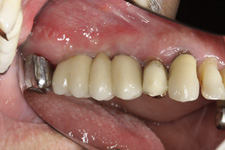

Náhrada jednoho zubu pomocí implantátu je možná také v postranním úseku chrupu. Při ztrátě většího počtu zubů ve frontálním nebo postranním úseku může být mezer uzavřena větším počtem jednotlivých implantátů.

Při ošetření pomocí jednotlivých implantátů zůstávají sousední zuby neporušené – intaktní. Při klasickém ošetření pomocí můstků musejí být tyto zuby obroušeny!

Protetické řešení může být pomocí můstku, který je kotvený na implantátech nebo pomocí jednotlivých korunek na implantátech.

- korunkami. Korunky nebo můstky mohou být na implantáty nacementovány nebo přišroubovány.